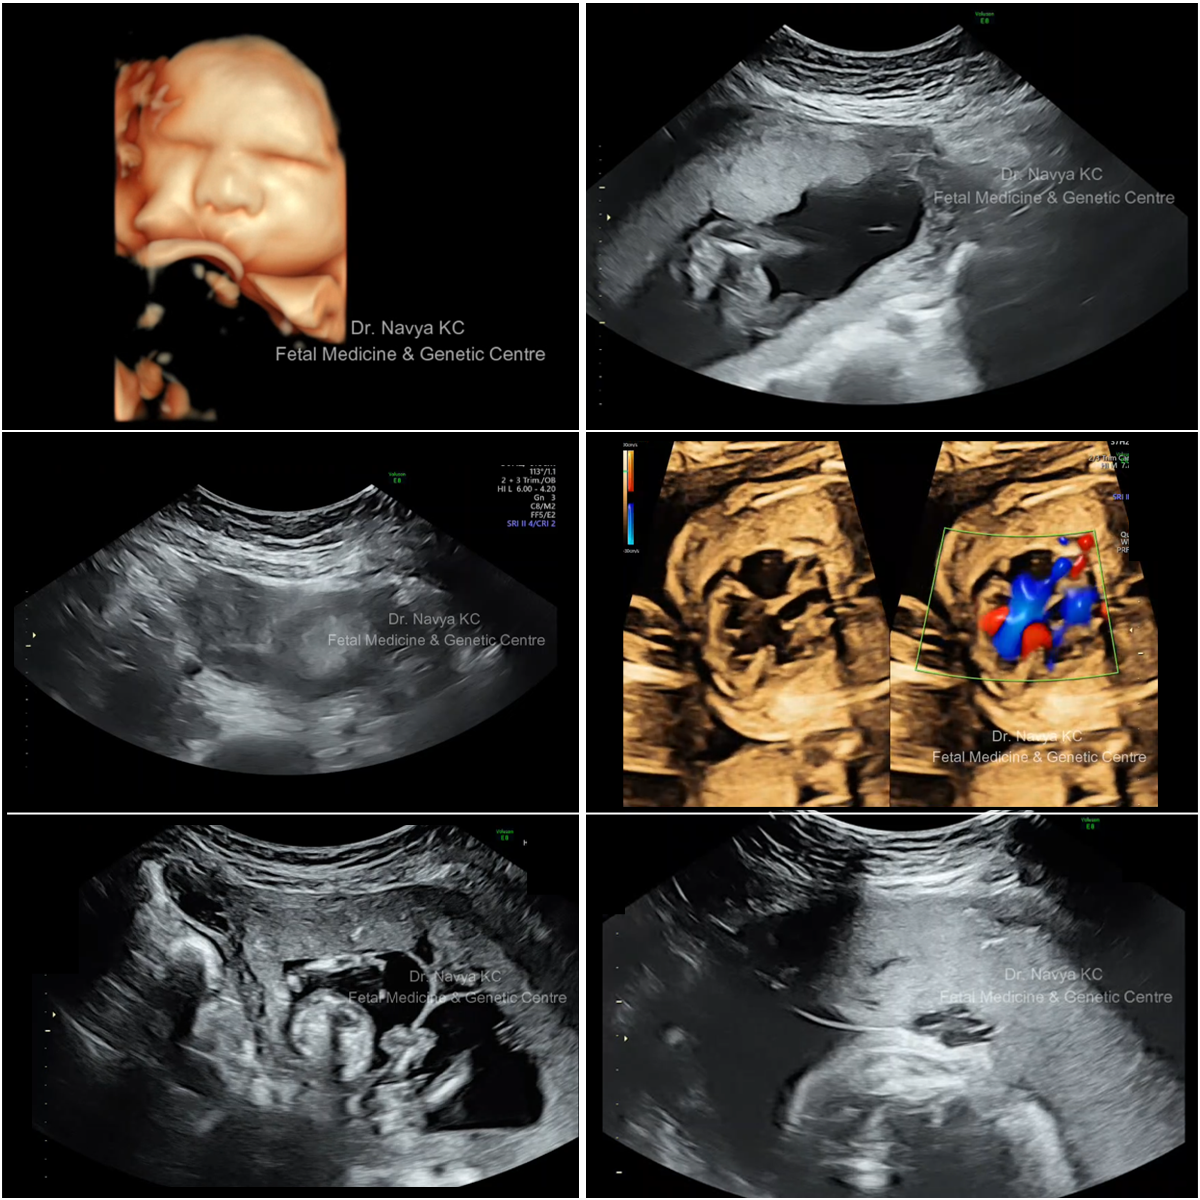

FETAL PROCEDURES (DIAGNOSTIC & THERAPEUTIC)

1. Amniocentesis

2. Chorion Villous Sampling (CVS)

3. Fetal Reduction

4. Cordocentesis

5. Shunt Insertion (Bladder And Thorax)

6. Amniodrainage

7. Amnioinfusion

8. Intrauterine Transfusion

9. Radio-frequency Ablation

Amniocentesis is the procedure where fluid around the baby in the womb (amniotic fluid) is aspirated by inserting a very thin needle in mother’s abdomen (like taking a blood sample from the arm). The procedure is associated with a small risk of miscarriage (0.1%) above the background risk.

CVS is the procedure where sample form placenta is obtained by inserting a very thin needle in mother’s abdomen. The procedure is associated with a small risk of miscarriage (0.1%) above the background risk.

In cases of more than two fetuses, risk for preterm delivery and associated morbidity and mortality is greatly increased, and fetal reduction gives the chance to reduce the pregnancy to twins. Procedure associated risk of miscarriage is 5%, but it improves intact survival and overall take home baby rate.

Cordocentesis is done to obtain fetal blood in cases of fetal anaemia, risk of haemoglobinopathy / metabolic disorders, at times for fetal karyotype if amniotic fluid is scanty.

In case of bladder outlet obstruction in fetus, selected cases can be shunted to preserve renal morphology. Thoracic shunts are used in case fetal hyrothorax but no other obvious structural malformation / CCAM.

Involves aspirating excess of fluid in cases of polyhydramnios to reduce maternal discomfort or prevent premature delivery.

Is done in cases of severe oligoamnios, to improve the visualization of fetal anatomy.

In cases of fetal anaemia, like, Rh isoimmunisation; cross-matched blood is given to the fetus in – utero.

Radiofrequency ablation (RFA) is a minimally invasive procedure that may be preformed in utero for Monochorionic Monoamniotic (MCDA) twin in which one fetus is very sick due to any anomaly, selective fetal growth restriction (s FGR), deformed twin like TRAP is selectively reduced using RF thereby places other baby from danger of death or permanent brain injury.